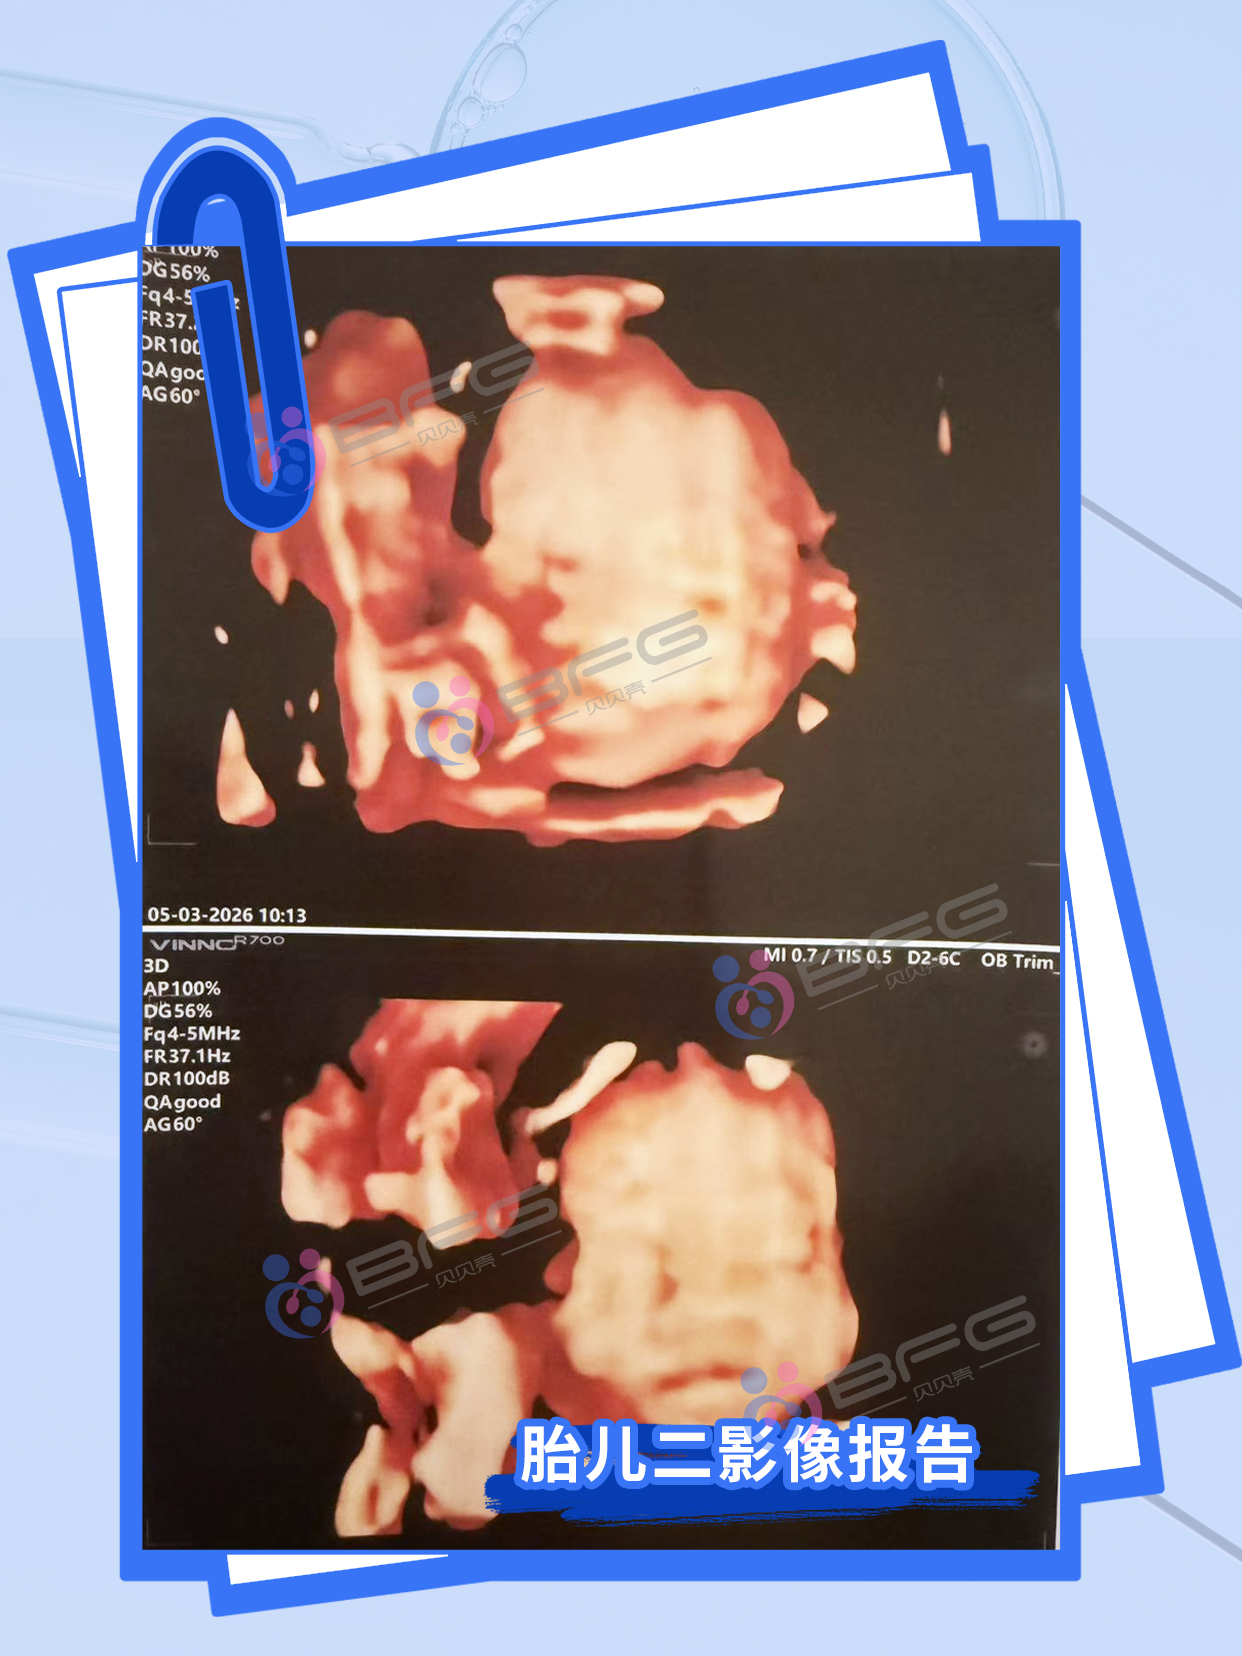

双胎24周,超声通关!两个小宝贝同步茁壮成长,各项指标棒棒哒~ 期待健康双倍惊喜!